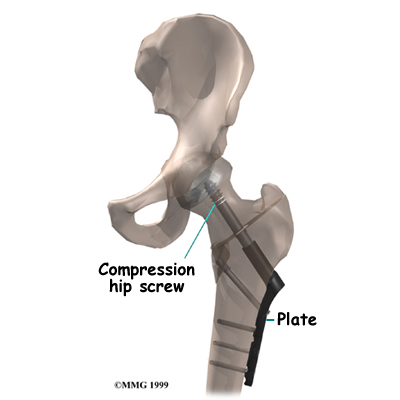

A fractured hip can be a life-threatening problem. The hip fracture itself isn't usually a difficult problem to treat with surgery. But once the fracture occurs, it brings with it all the potential medical complications that can arise when aging adults are confined to bed. The goal of treatment is to get patients moving as quickly as possible after surgery. Fixing the fracture with a compression hip screw and metal plate is fairly simple and usually allows patients to get up and start moving shortly after surgery.

Fixing the hip fracture surgically with a special type of metal plate and screw, called a compression screw, does two things. First, it helps align the bone fragments and hold them in the proper position. Second, the fixation device is strong enough to keep the bones in place as you begin to move about. Before these devices were used, a patient needed to remain in bed usually with traction to hold the bones in alignment. The fixation now holds the bones in place while the bone heals. This allows you to get out of bed sooner because the metal plate and screw are strong enough to hold the bone fragments in place as you move.

Next, the surgeon makes an incision over the side of the thigh. A large metal screw is placed through the side of the hip into the femoral head. With the help of the fluoroscope, the surgeon attaches a metal plate to the side of the femur with four to eight small metal screws. The procedure can usually be finished in less than an hour depending on how many fragments of bone are involved in the fracture.